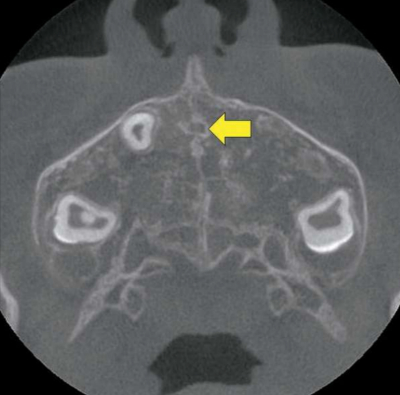

顔面部の歯科用コーンビームCTを別に示す。矢印で示すのはどれか。1つ選べ。

a. 切歯管

b. 翼突管

c. 眼窩下管

d. 小口蓋管

e. 大口蓋管